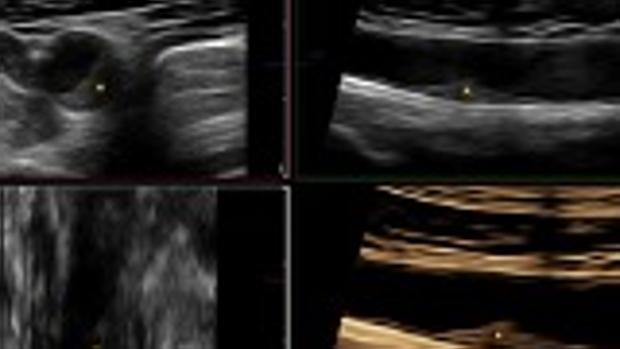

06/04/2020 22:28h. La grasa de las arterias se acumula de forma rápida en personas sanas a partir de los 40 años S. Mencia